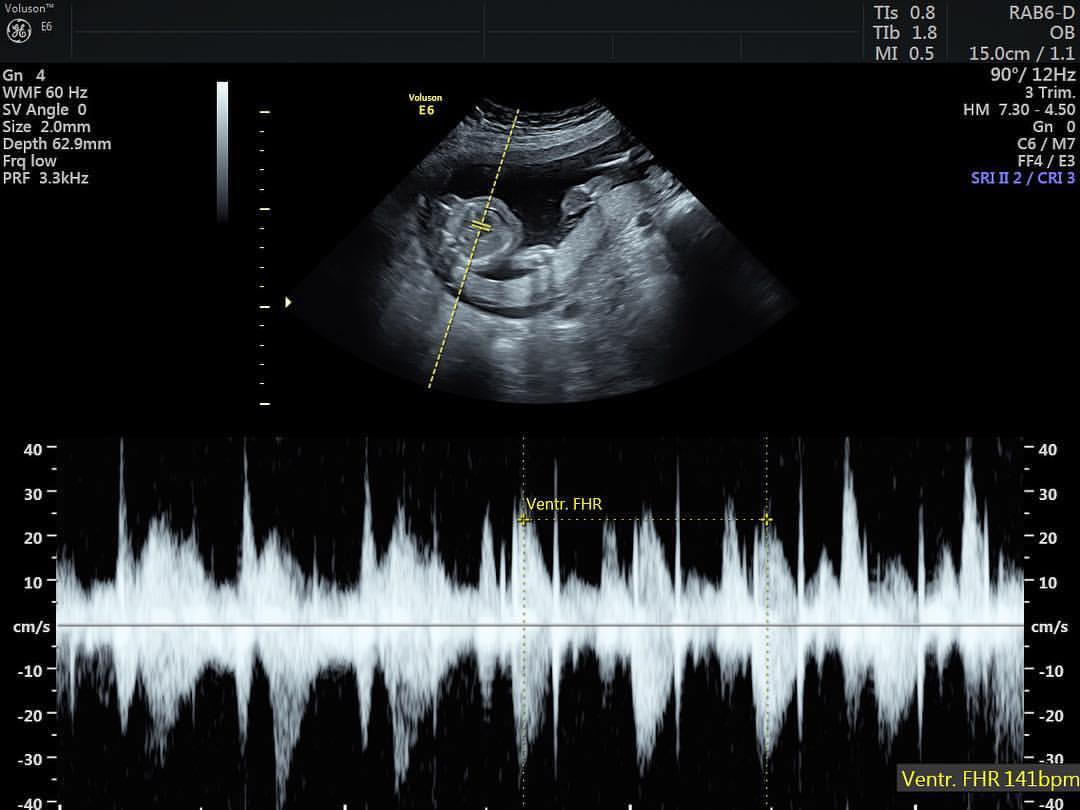

“Questo è il perfetto cuore di nostra figlia. Ha piedi, mani, reni e fegato perfetti. Sfortunatamente non ha un cervello perfetto”, ha scritto su Facebook Keri, pubblicando l’immagine dell’ecografia. “Mio marito ed io abbiamo deciso di portare a termine la gravidanza perché così Eva potrà dare la vita ad altre persone attraverso la donazione di organi. Non è stata una decisione facile. Per le prossime venti settimane sentirò i suoi calcetti e il battito del suo cuore, tutto sapendo che mio marito ed io avremo solo poche ore con lei. (…) Siamo devastati, ma stiamo cercando di provare a vedere gli aspetti positivi di questa situazione e di apprezzare il nostro tempo con Eva, e di essere grati per l’impatto che lei avrà sul mondo nel breve lasso di tempo che passerà qui”.